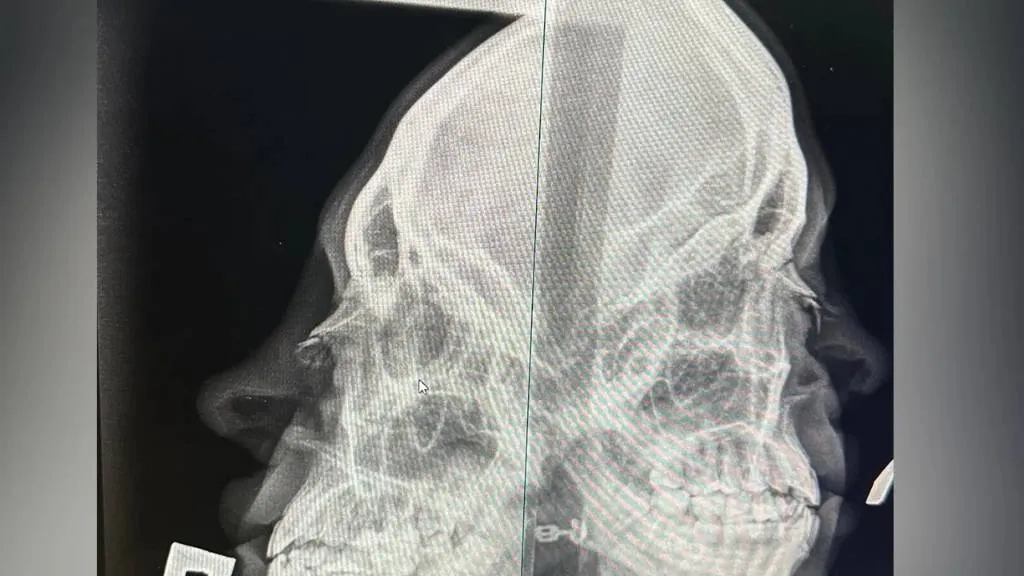

Посетитель бара в Челябинске, который сломал нос девушке-хостес. Фото © Telegram / SHOT

Как оказалось, мужчина с одного удара сломал хрупкой девушке нос: в больнице ей сообщили, что требуется операция. Пострадавшая написала заявление в полицию. Неадекватного бойца сейчас разыскивают.